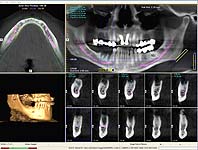

DVT mit 3D-Planung